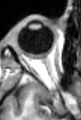

- The optic nerve on MRI